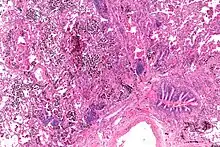

Micrograph showing a pulmonary hemorrhage. H&E stain.